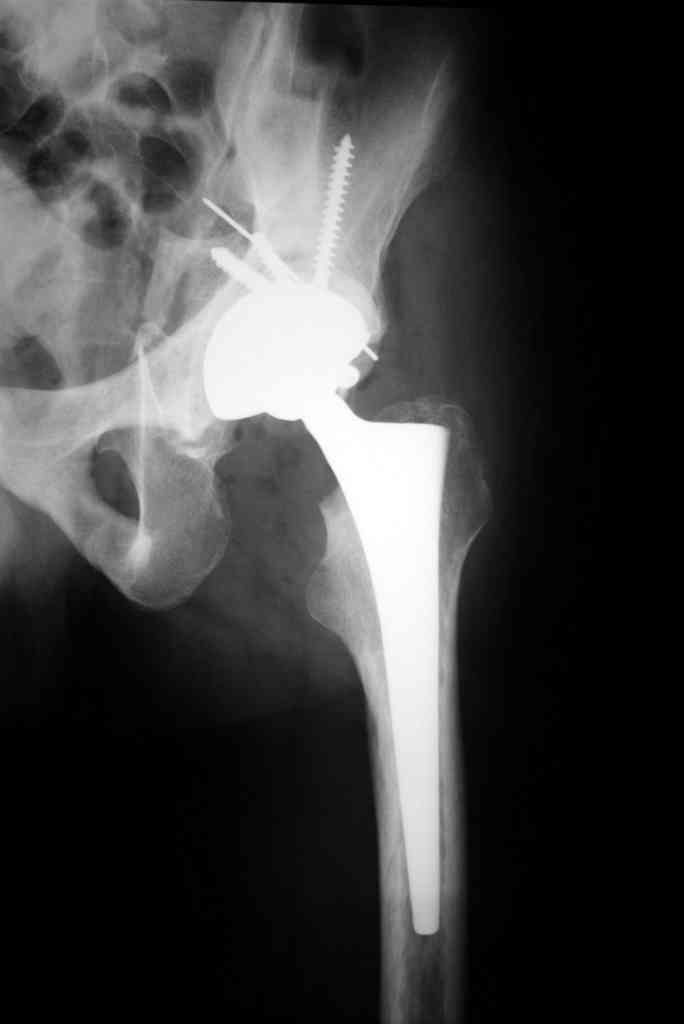

К сожалению, нередкая ситуация, мы предпочитаем выполнять операцию одномоментно - пластика задне-верхнего дефекта крыши ВВ собственной

головкой, установка вертлужного компонента бесцементной фиксации с обязательной дополнительной фиксацией винтами. Проблема будет в

восстановлении длины ноги, опыт показывает, что более 3-х см одномоментно восстановить очень сложно, и даже для этого потребуется широкая мобилизация бедра. В одном из номеров ж-ла Ортопедия травматология России мы опубликовали наш подход и р-ты лечения у больных с последствиями перелома ВВ.

Прилагаю в качестве иллюстрации одну из последних операций.